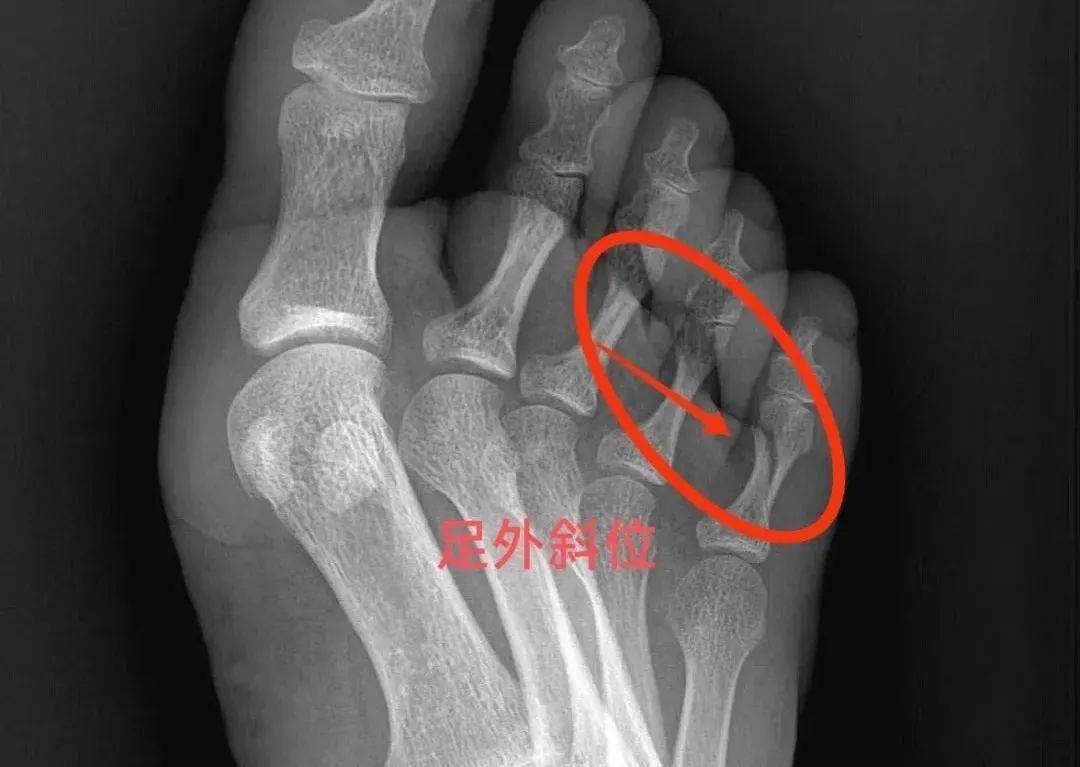

典型病例-3(右手第三,四,五掌骨头骨折)